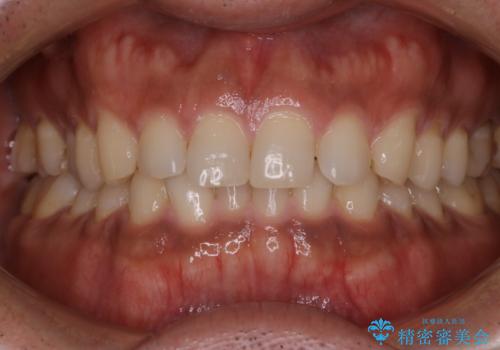

- 20代男性

- 1日

- 1回

- 数年ぶりにホワイトニングを希望とのことで、できる限り白くしたいとのことでした。

オフィスホワイトニングのエクセレントコースを行いました。

- ¥29700費用は治療当時の料金となります